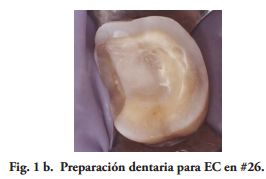

Al momento del examen, 10 (90.9%) EC estaban en función en 10 pacientes. Un molar 26, restaurado con EC, se perdió por enfermedad periodontal después de 12 años y 9 meses en función. Ninguna restauración se desprendió, no hubo recidiva de caries y al examen radiográfico no se observaron lesiones patológicas en los 10 DPET en función (Figs. 1a,1d; 2c; 3c,3d; 4c).

Las paredes internas de la corona dentaria y de la cámara pulpar, deben tener una divergencia hacia oclusal mayor de 60 y si presentan depresiones o zonas retentivas, deben rellenarse con cemento de ionómero de vidrio. El operador, dispensa una fina capa del mismo cemento en el piso cameral. En este estudio cuatro preparaciones tenían 3 paredes coronarias (Figs. 1b, 2a), cuatro 2 paredes (Fig. 3a) y en 2, las restauraciones abarcaban 4 paredes coronarias.